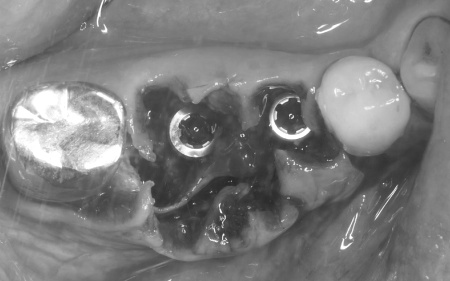

そこで歯ぐきの一部を開き内部を直接確認したところ、いずれの歯根が垂直方向に割れていました。

まず右下奥歯2本の抜歯を行い、その後、約3ヶ月間歯ぐきや骨が十分に回復するのを待ちました。

完成した治療計画をもとに、インプラントをあごの骨に埋める手術を実施しました。

一定期間をおいてインプラントがあごの骨に定着したことを確認したあと、歯ぐきの上にインプラントの一部を出すための二次手術を行いました。